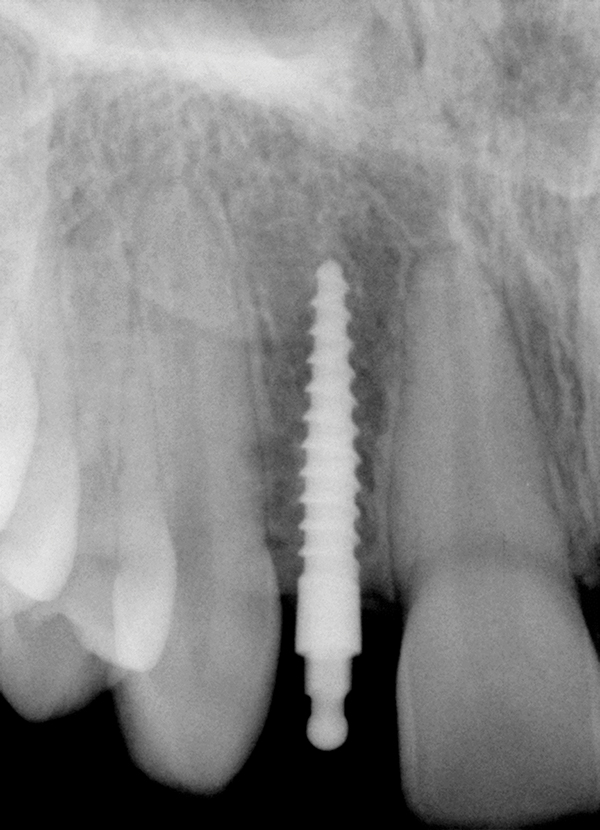

Un pacient cu istoric medical neremarcabil s-a prezentat cu o punte Maryland eșuată care înlocuia dintele 4.1. Spațiul interdentar corespunzător poziției 4.1. era de cca 5 mm, fiind inadecvat pentru un CDI (fig. 14). S-au prezentat și dezbătut opțiuni terapeutice non-implantare, pacientul insistând pentru o restaurare fixă cu sprijin implantar. Datorită spațiului interdentar limitat, clinicianul a stabilit necesitatea unui MDI.

Înainte de a continua cu opțiunea MISFR, clinicianul a discutat posibila complicație de lezare a rădăcinilor adiacente în cursul inserării implantului, ce ar impune tratament endodontic ulterior sau posibilă extracție. Pacientul a decis să continue cu această opțiune.

S-a plasat un MDI (fig. 15), radiografiile periapicale confirmând traiectoria adecvată a implantului. Pacientul a refuzat restaurarea provizorie din cauza costului implicat. S-a fabricat o coroană PFM finală și s-a cimentat cu rășină. După 8 ani de funcționare a MISFR, pacientul nu a raportat nicio complicație.